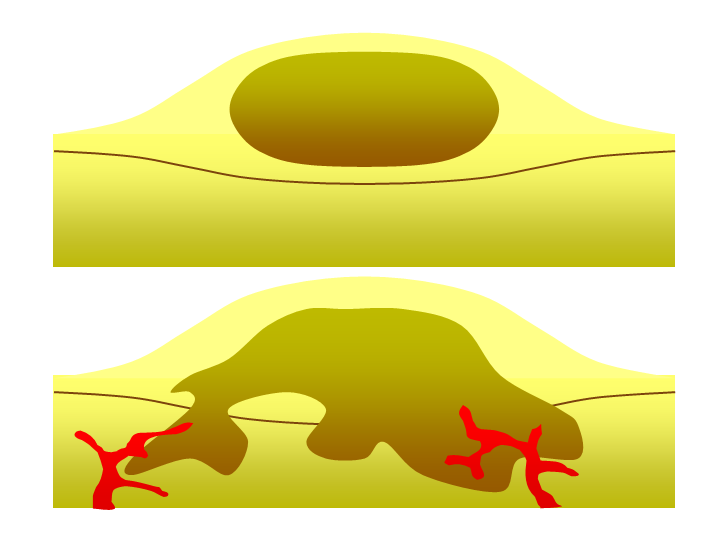

Benign tumor (top) versus malignant tumor (bottom).

Certain types of benign (non-cancerous) lung tumors can show up as pulmonary nodules on scans. These tumors are generally made up of a disorganized mass of cells, but but they do not grow or spread like cancerous tumors do.

Because they are so small, pulmonary nodules caused by benign tumors don't usually cause any symptoms. Most are harmless growths that can be left alone without any further treatment.

However, if a nodule forms in certain places in the lung (e.g. near an airway opening), it can obstruct airflow and cause respiratory symptoms. If this happens, or the tumor causes other symptoms, you may need to have it removed through surgery.